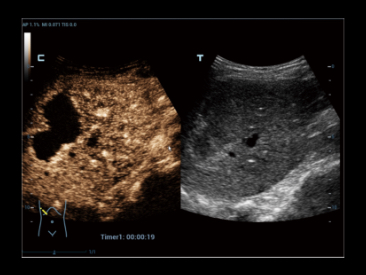

Potenciada por la tecnologĂa ZST+ y la ecografĂa de contraste mejorada (CEUS) basada en ondas planas, la HiFR CEUS permite que la ecografĂa de contraste mejorada ultrarrĂĄpida, para la visualizaciĂłn de la estructura vascular y perfusiĂłn en fase arterial, funcione como una herramienta complementaria de UWN+ (ultra-wideband nonlinear contrast imaging).

Caso HiFR CEUS: HNF de hĂgado

*No se recomienda aplicar HiFR CEUS en fase de retardo o en una regiĂłn de 10 cm de profundidad